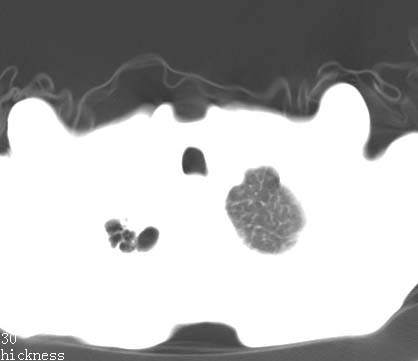

病人女 60岁 咳嗽 气促十余天,大叶性肺炎.

右肺上下叶均见 大片状密度增高影,边界清晰,其内可见支气管充气征,气管支气管通畅。纵膈略向右移位,其内无肿大淋巴结影。首先考虑炎性病变。不排除一些特异性的炎症。不知道发烧吗??wbc高吗??建议治疗后复查!!

看影响还是首先考虑炎性改变,建议实验室检查,还有要警惕炎性肺泡癌,具有的枯枝征象。

右肺感染性病变(大叶性肺炎可能);建议抗炎治疗后复查。

看影像还是首先考虑炎性改变,建议实验室检查,还有要警惕炎性肺泡癌,具有的枯枝征象